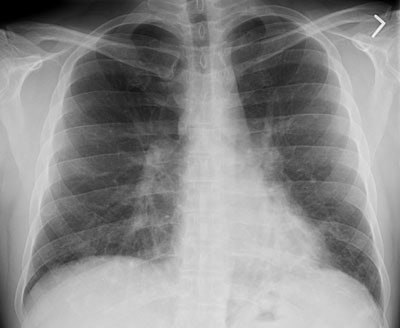

The patient below presented with complaints of cough, malaise, and a low-grade fever. The chest radiograph revealed some patchy left lower lobe airspace disease and vague nodular shadows- particularly in the lower lung zones. A chest CT was performed and demonstrated multiple nodular airspace abnormalities with variable margins. The lesions did not improve despite antibiotic therapy and all cultures were negative. Click images to enlarge.